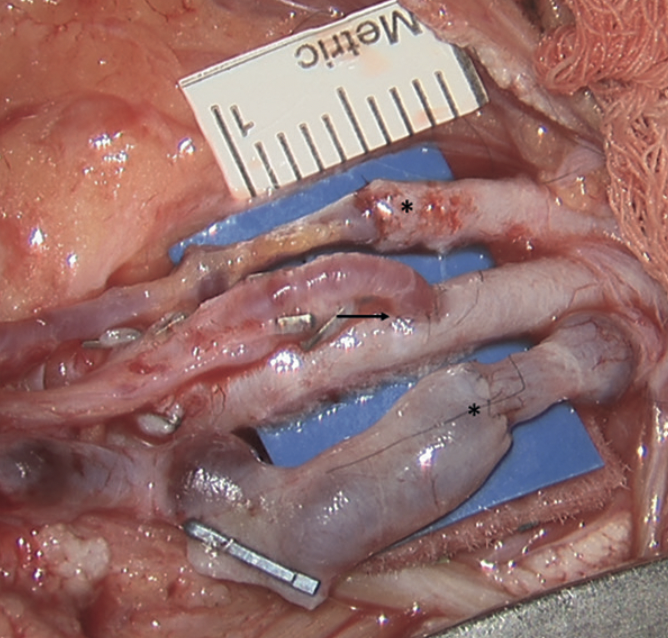

Manuel Antonio Grez ibàñez, Luis Gerardo Antequera Velásquez

|

|

|